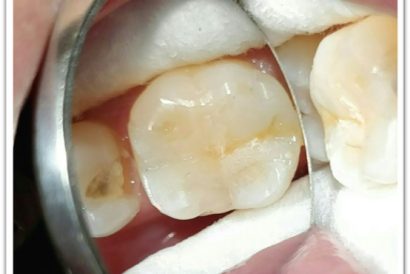

Patient Name:Akshay Gharat

Tooth Involved :16

Diagnosis :Caries Involving Enamel And Dentin Mesiocclusally

Treatment :Class Two Direct Composite Restoration Using Nanohybrid Composite

Before

After

Patient Name:Rakesh Sinha

Tooth Involved :46

Diagnosis :Distocclusal Caries Involving Enamel And Dentin

Treatment :Indirect Restoration With Cuspal Coverage Of Distocclusal Cusp